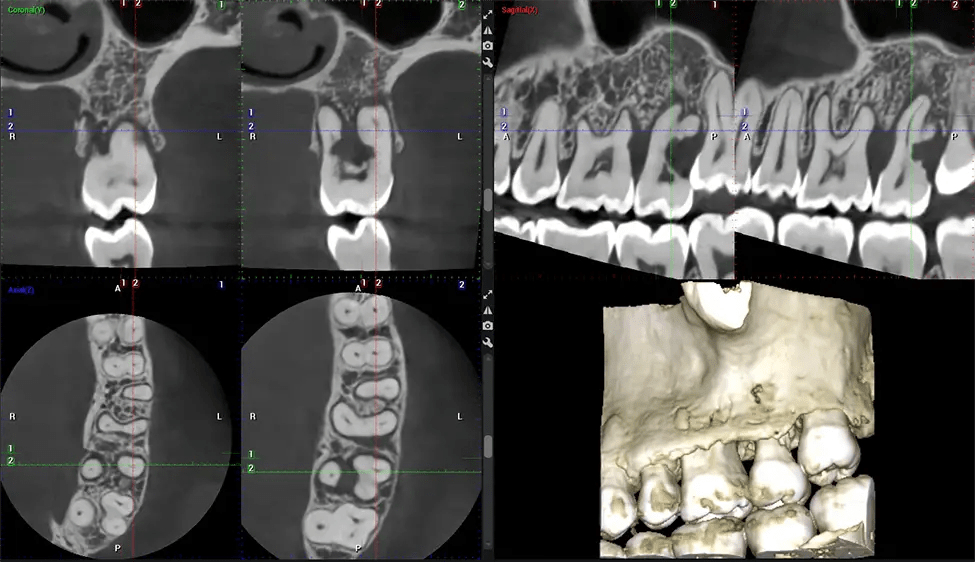

This 3D scan, called cone beam computed tomography, gives your dentist a more complete image of your oral anatomy and disease processes than a traditional X-ray. Unlike conventional X-rays, which capture a 2D image of your mouth from various angles, a 3D scan takes multiple digital X-rays for one image. It provides a complete view of your jaw, teeth, nerves, and soft tissues. This enhanced view allows dentists to detect minor issues not visible in traditional 2D scans, such as impacted wisdom teeth or bone fractures in the sinus cavity.

There are many benefits to using CBCT technology, especially compared to the traditional 2D X-ray format. One of the most significant advantages of CBCT scans is that they provide much more information than traditional X-rays. A scan lets your dentist see images from all angles of your jaw and mouth, including your sinuses, nasal cavity, cheekbones, and other surrounding areas. This added information helps your dentist craft a comprehensive treatment plan that addresses all aspects of your oral health.

Another significant benefit is that 3D imaging provides more precise images of your bone structure. These images are more detailed, providing you with a more accurate diagnosis. An accurate diagnosis means better treatment for you.

Our patented SCARA technology enables doctors to capture True Extraoral Bitewings that are as accurate at detecting caries as a 2D bitewing series, but with half the radiation dose. With our bitewings, doctors can view the apices of teeth on both jaws providing a more comprehensive view of the patients’ anatomy.

Planmeca 3D systems come with Autofocus, a technology that produces incredibly clear panoramic images, even on the interiors. This technology sets our 2D images apart from the competition.